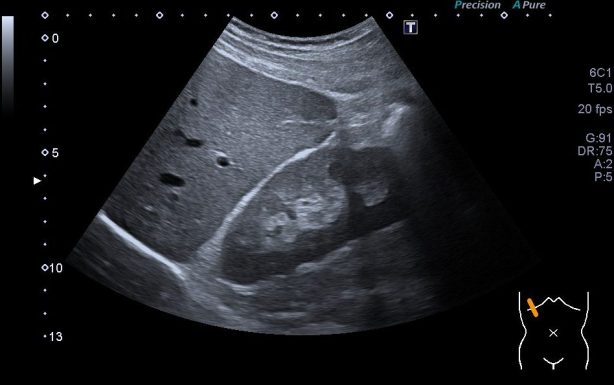

324. Hepatopatía crónica por ecografía.

A veces es un hallazgo casual. Descubrir cambios en la ecogenicidad hepática es una semiología que tenemos que tener muy muy claro, para ello lo primero que tenemos que hacer es identificar correctamente una semiología normal hepática que en muy pocas palabras tiene que ser así:

1. Parénquima hepático homogéneo

2. Bordes lisos.

Siempre digo que estudiar el hígado es una de las partes más difíciles de la ecografía abdominal, percibir pequeños cambios en el parénquima a veces no es fácil. Por eso estas dos indicaciones de arriba te van a ayudar. Es interesante que posicionemos al paciente en decúbito lateral izquierdo para estudiar el borde derecho hepático que a menudo puede quedar oculto en decúbito supino.

La imagen que debes de conseguir en una imagen normal del hígado es el en lóbulo hepático derecho y sería esta:

Por tanto y atendiendo a la semiología normal, el hígado afectado por una hepatopatía crónica tendrá una ecogenicidad alterada y en nuestro documento de información al radiólogo deberemos reflejar dos hallazgos principales:

1. Heterogeneidad parenquimatosa

2. Bordes o contorno hepático lobulado

Quizá el punto número dos sea el más definitivo, por eso siempre es muy importante perder el tiempo en «pintar» muy bien el hígado pasando nuestra brocha por todos lo bordes, para que el trabajo sea perfecto y todos los detalles sean explorados.

La imagen típica de hepatopatía crónica sería esta:

Puedes observar la superficie hepática en forma de olas y la heteroecogenicidad del hígado..

Compara la dos imágenes y percibe los cambios, así podrás reconocer siempre estos cambios.

Es importante por último, preguntar al paciente si tiene hábitos enólicos, es nos dará pista sobre estos hallazgos y si es un hallazgo casual, obviamente debe ser estudiado.